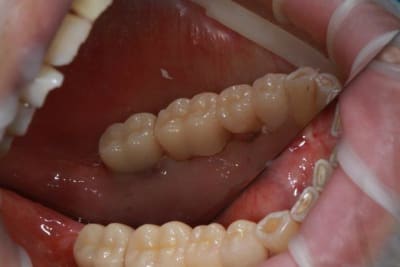

Ce matin repose d'un nouvel implant et comme je ne veux pas prendre de risque, et que les dents adjacentes doivent être couronnées, je pose un bridge en emax press, mais scellé au ciment provisoire...

Si l'implant va bien le bridge sera déposé, coupé, et 44/46 seront collées définitivement après traitement acide et silane.

alors là pas du tout, le patient vient me voir pour des implants, donc je fais une étude du cas absence des molaires supérieures, couronnes mandibulaires très ancienne 45 racine cassée, 44 dévitalisée mais passablement déchaussée, donc avulsion de 45 et pose d'un implant avant de refaire les couronnes 46/47 et l'ensemble.

Dépose gratuite bien sur et repose gratuite aussi, le bridge n'est pas facturé non plus, il le sera sous forme de 2 couronnes que cette fois ci l'implant fonctionne ce que j’espère, ou laissé en bridge si l'implant devait être retiré.

Le fait de scellé au ciment temporaire ne pose en principe pas de problème pour 3 à 6 mois.